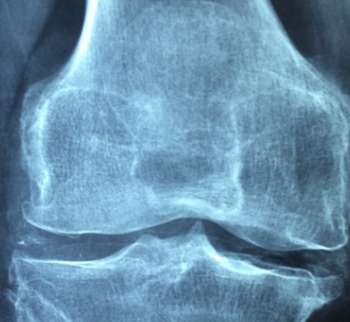

비타민D 부족 증상 10. 골다공증

비타민 D가 부족하면 골다공증 위험이 증가합니다. 비타민 D는 칼슘 흡수를 돕고, 뼈의 형성과 재생을 촉진하여 뼈의 밀도를 유지합니다. 비타민 D가 부족하면 뼈가 약해지고, 골밀도가 감소하여 골다공증이 발생할 수 있습니다. 이는 골절 위험을 증가시키고, 특히 고령자들에게는 심각한 건강 문제를 초래할 수 있습니다. 골다공증 예방을 위해서는 비타민 D와 칼슘을 충분히 섭취하는 것이 중요합니다.